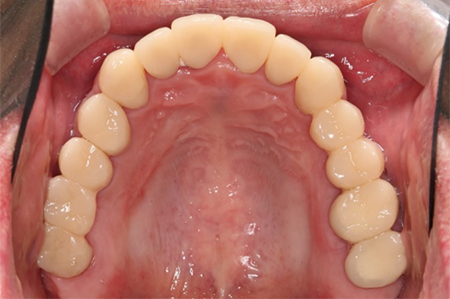

この患者様は長い事歯科医院には通っておらず、下の歯は前歯以外は全て崩壊していることが分かります。

前から見ても歯が欠けてしまい、歯茎も赤く腫れてしまっているのが分かります。

一般的には入れ歯が妥当かと思われますが、患者様は33歳、まだまだ人生は長いです。

奥歯がないと前歯でしか噛めなくなってしまい、残っている前歯もいずれダメになってしまいます。

また、奥歯がなくなってからの期間が長かったため、入れ歯が入るスペースが奥にないのが分かります。

様々なことを鑑み、患者様とも何度も話し合いを行い、下の奥歯には必要最低限のインプラントを、他の歯も外科処置を施しなるべく歯を抜かない方法を取りました。

最終的に抜歯した本数は下の歯5本。上の歯に関しては全て残すことが出来ました。

奥歯があることで前歯の負担を減らし、前歯を失うリスクを下げることが出来ます。